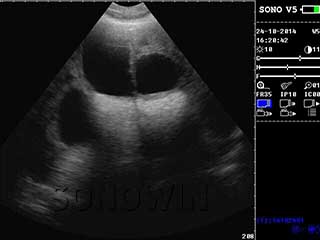

优质图像